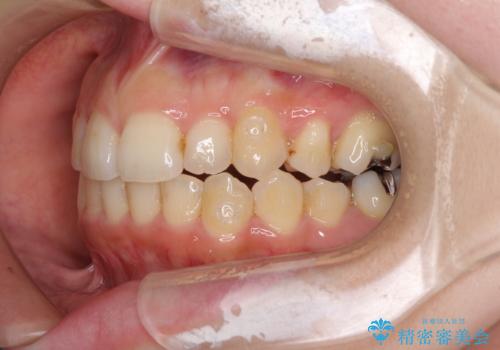

- 顕著な八重歯など、上下前歯のデコボコとスペースを気にして来院された患者様です。

八重歯改善には第一小臼歯の抜歯が必要であり、移動量が多いことから補助装置により八重歯を引き込むこととしました。

インビザラインでの治療をご希望であったので、インビザラインにて行うこととしましたが、右側前歯の改善にはワイヤー矯正が必要となる可能性があることをお伝えした上で治療を開始しました。

補助装置だけでなく、部分的にワイヤー矯正も使用しましたが、上下のスペースは改善しきれず、側切歯(前から2番目の歯)や顕著な八重歯は、インビザラインで治療するには限界があることがよく分かりました。

より良い仕上がりを希望される場合には、ワイヤー装置による矯正治療がお勧めとなります。